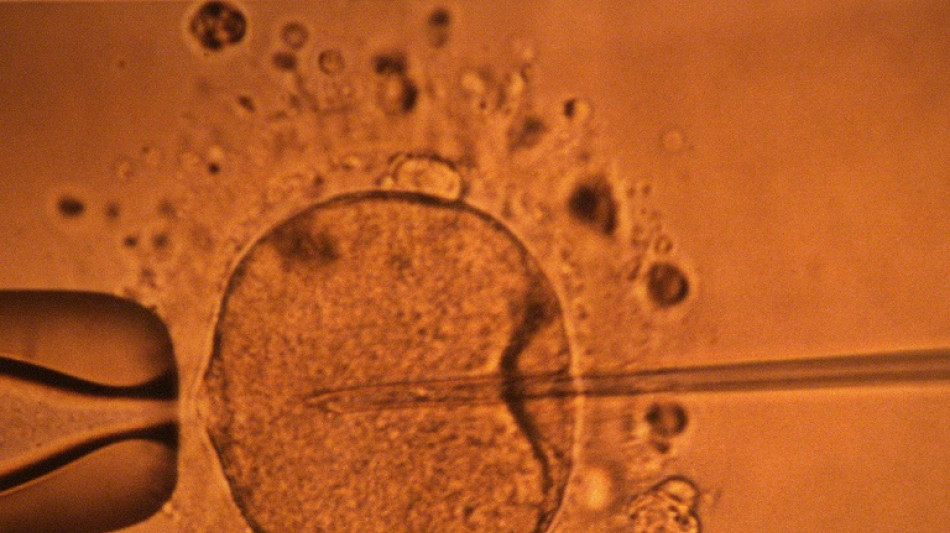

Un estudio apoya hipótesis de disminución mundial de concentración de espermatozoides

La concentración de espermatozoides, uno de los factores de la fertilidad masculina, disminuyó significativamente en todo el planeta en las últimas décadas, según un estudio publicado el martes.

"La concentración de espermatozoides disminuyó significativamente entre 1973 y 2018", resumen los autores de este trabajo publicado en la revista Human Reproduction Update y realizado mediante la compilación de unos 40 estudios previos.

Esta publicación es de una magnitud sin precedentes sobre el tema, aunque confirma las conclusiones de una investigación anterior del mismo equipo, dirigido por el epidemiólogo israelí Hagai Levine.

Esta última, publicada en 2017, había sido objeto de varias críticas, en particular porque sus conclusiones sólo afectaban a algunos países occidentales.

Esta vez, después de haber incorporado más datos, los autores pueden concluir que la tendencia a la baja también afecta a América del Sur, Asia y África.

"Además, los datos sugieren que este declive mundial continúa a un ritmo acelerado desde principios del siglo XXI", escriben.

La cantidad de espermatozoides es uno de los factores que afectan a la fertilidad masculina, pero no es el único.

Su movilidad también desempeña un papel crucial, pero esta característica no se mide en este estudio. Por ello, no se puede concluir que haya una disminución general de la fertilidad masculina, aunque la investigación aporta elementos en este sentido y se suma a otros trabajos que estudiaron las causas de esta tendencia.

Como posibles causas a este fenómeno, se contemplan "la obesidad, la falta de actividad física, la contaminación y la exposición a productos químicos en el medio ambiente", recordó la endocrinóloga Channa Jayasena.